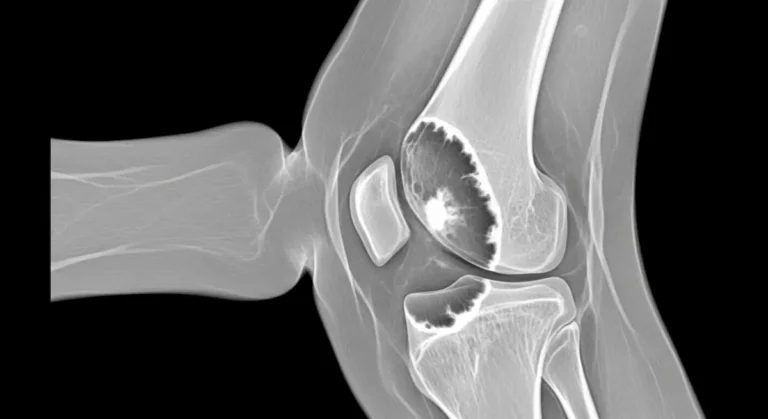

Síndrome de Ahlback: causas, sintomas e tratamento

A síndrome de Ahlback descreve uma lesão do osso subcondral no joelho, geralmente no côndilo femoral medial, com dor súbita…